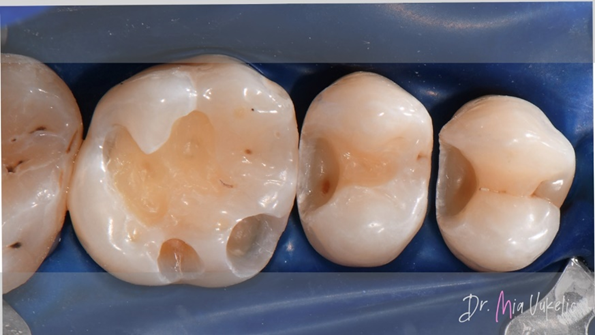

After proper isolation with a rubber dam and placement of wedges, the cavity preparation began with a cylindrical bur. Following the removal of the restoration, we proceed to eliminate demineralized dentin using a steel bur. The final cavity refinement involved converting convergent walls into divergent ones and polishing the internal cavity surface with diamond polishing burs.

![]() |